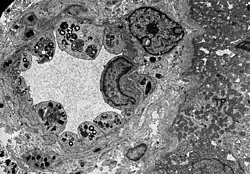

Wie die meisten Symptome bei Morbus Fabry weist auch die Schädigung der Nieren einen progressiven Verlauf auf. Er endet mit dem terminalen Nierenversagen und bewirkt eine deutlich reduzierte Lebenserwartung.[70] Bei dem klassischen Krankheitsbild des Morbus Fabry führen die Gb3-Ansammlungen in den Endothelzellen des Glomerulums, in den Mesangiumzellen, in den Podozyten und in den Zellen des Interstitiums zur Schädigung der Niere.[71] Bei diesen Zellen handelt es sich um ausdifferenzierte Epithelzellen. Auch im Epithel der Henle-Schleife und des distalen Tubulus sowie im Endothel und den Zellen der glatten Muskulatur der Arteriolen der Niere finden sich Glycosphingolipid-Ansammlungen.[72][73] Im Transmissionselektronenmikroskop (TEM) sind die Gb3-Ablagerungen im Zytoplasma gut zu erkennen. Sie haben die Form von Myelinstrukturen und stoßen an den Zellkern. Mit zunehmender Gb3-Akkumulation wird das Mesangium aufgeweitet, worauf eine segmentale oder globale Glomerulosklerose mit Eindickung der Basalmembranen erfolgt.[74] Mikrovaskuläre Läsionen und Schädigungen der für die Filterleistung wichtigen Podozyten sowie der Epithelzellen des Tubulus werden dabei als mögliche Mechanismen diskutiert.[75]

Die TEM-Aufnahme zeigt die massive elektronendichte (= schwarze) Ansammlung an Glycosphingolipiden im Lysosom der Podozyten. -

Ebenfalls eine TEM-Aufnahme. Sie zeigt die Inklusionen von Glycosphingolipiden unterschiedlicher Form und Größe in den Zellen des distalen Tubulus. -

TEM-Aufnahme von den Endothelien und Zellen der glatten Muskulatur einer Nierenarteriole mit Inklusionen von Glycosphingolipiden